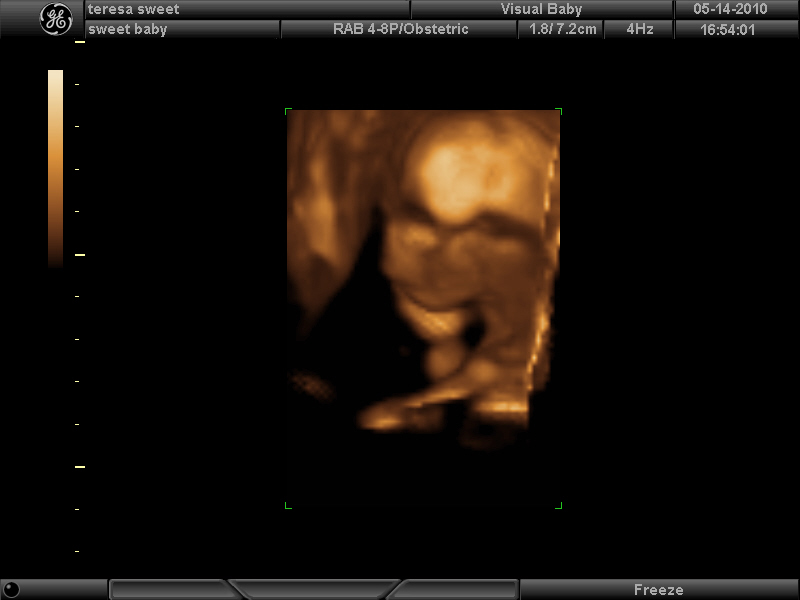

Here’s a few photos in 3D. I’m 17 wks now.

So baby was very very stubborn. Sleeping at first, cord between its legs, not moving much, curled up in a ball, etc etc. lol